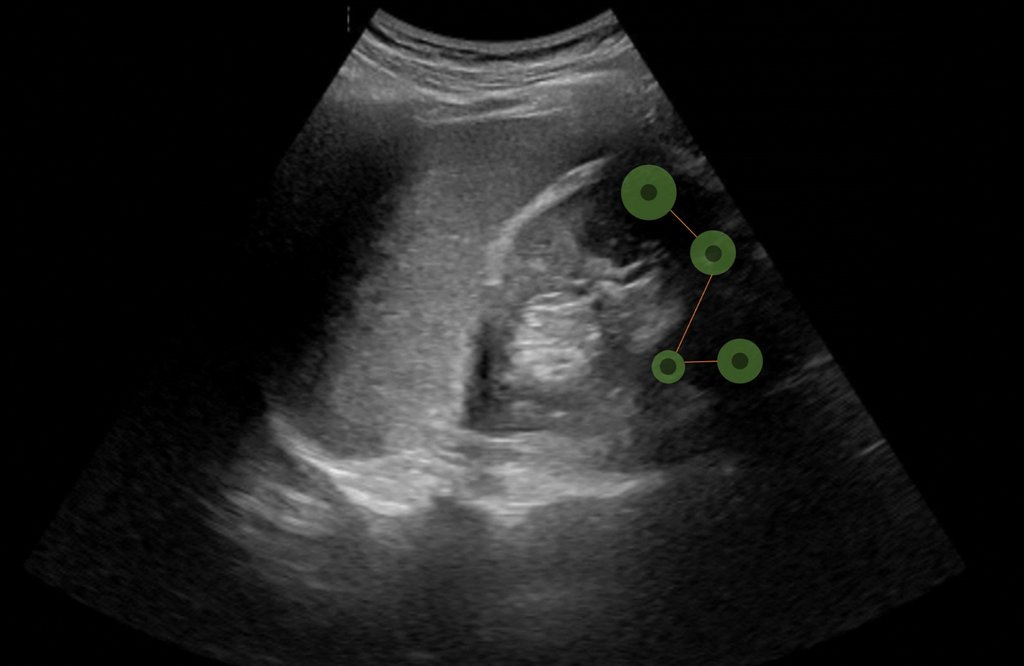

The Training Centre of HOCH Health Ostschweiz (STZ-HOCH) and the Institute of Computer Science (ICS-HSG) at the University of St.Gallen are working together on the "ETATUS – Eye Tracking as an Assistance Tool in Ultrasound Training" project to develop innovative training approaches for point-of-care ultrasound (POCUS).

The aim of the project is to develop scientifically sound training methods that can be effectively implemented through evidence-based analyses. These methods should enable residents to quickly and more productively engage in everyday clinical practices, and thereby relieve the workload of trainers. The project thus lays the foundation for more precise diagnoses and optimized learning processes in the field of point-of-care ultrasound (POCUS).

Point-of-Care Ultrasound (POCUS) is a diagnostic ultrasound procedure used directly at the patient's bedside that places high visual and cognitive demands on the user. Eye-tracking technology makes eye movements visible and helps to optimize the learning strategies of residents in a targeted manner. Three key advantages are expected: